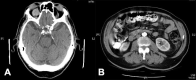

Intraocular lymphoma (IOL) is a rare and life-threatening condition whose aetiology is unclear. Blurred vision, reduced vision, and floaters are common initial symptoms. Posterior vitreous detachment and haemorrhage rarely occur. The authors present the case of a 79-year-old man who initially presented with a 3-month history of fever, night sweats, significant weight loss, bilateral peri-orbital haematoma, red eyes and retro-orbital headache. Physical examination revealed fever, bilateral peri-orbital haematoma, subconjunctival haemorrhage and palpable cervical lymphadenopathy. CT scans detected conical intra-orbital lesions, cervical adenomegalies, expansive lesions in the adrenal glands, and thrombosis of the splenomesenteric confluent and posterior segment of the right branch of the portal vein. These findings were suggestive of a lymphoproliferative disorder. Aspiration cytology of the adrenal mass and inguinal adenopathies was compatible with diffuse large B-cell lymphoma with areas of transformation to Burkitt's lymphoma. We describe a rare form of lymphoma, and a very unusual presentation of primary intraocular lymphoma with atypical symptoms.